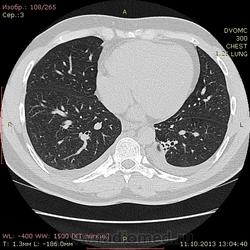

Пациент 35 лет. На УЗИ нашли житкость слева в плевральной полости, отправили на КТ - жидкость с обеих сторон. Из разговора с больным выяснилось, что около 1,5 месяцев назад была высокая тенпература, кашель - никуда не обращался и не лечился. На момент исследования ни на что не жалуется.

Похоже слева в S10? на поствоспалительные изменения? или на что похуже? И если на стороне поражения можно понять окуда жидкость, то справа - можно расценивать как реакция плевры на воспаление слева?

Локальный фиброз субсегмента S10 слева с бронхоэктазами. Двусторонний малый гидроторакс (толщина слоя жидкости до 1 см≈объём до 50 мл). Интересная субкапсульная ерундовина в S6 печени, наверное киста.